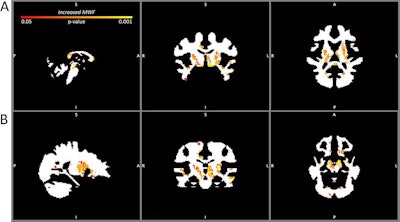

Compared with the baseline images from the healthy athletes, the contact sport athletes showed significantly higher myelin water fractions at baseline in the bilateral basal ganglia, anterior and posterior corpora callosa, left corticospinal tract, and left anterior and superior temporal lobe. What's more, they also demonstrated significantly higher myelin water fractions three months later in the bilateral basal ganglia, anterior and posterior corpora callosa, and left anterior temporal lobe, as well as in the bilateral corticospinal tracts, parahippocampal gyrus, and bilateral juxtaposition areas, according to the researchers.

The contact sport athletes also had higher overall myelin water fraction at the time of injury and three months later, compared with the healthy athletes. The increases in overall myelin water fraction were greatest in the bilateral basal ganglia and deep white matter, while decreases were seen in more superficial white matter, the researchers found.